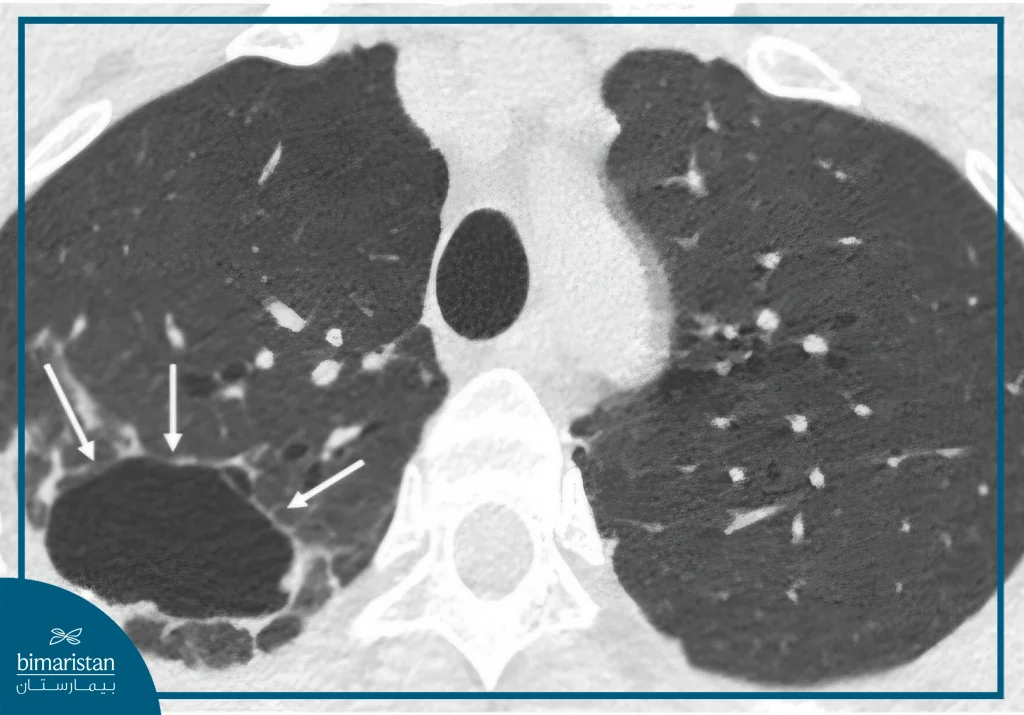

2. اكتشاف عُقيدات رئوية صغيرة

يُعدّ ظهور عقيدة رئوية صغيرة (Lung Nodule) من النتائج الشائعة جداً، وتُرصد لدى نحو نصف الأشخاص الذين يخضعون للفحص. غالبية هذه العقيدات غير سرطانية، وقد تمثل بقايا التهابات قديمة أو تليّفات بسيطة في نسيج الرئة. في هذه الحالة، لا يُتخذ إجراء فوري، بل يُوصى بإعادة الفحص بعد فترة تتراوح بين 3 إلى 12 شهراً لمراقبة حجم العقدة والتأكد من ثباتها.

إذا بقيت ثابتة الحجم، تُعتبر سليمة، أما إذا أظهرت زيادة تدريجية في الحجم، فقد يوصي الطبيب بإجراء فحوص إضافية مثل:

- تصوير مقطعي متقدم لتقييم النمو بدقة

- فحص PET-CT لتمييز النشاط الخلوي

- خزعة رئوية لأخذ عيّنة وتحليلها في المختبر عند الشك القوي بالسرطان

3. وجود عُقيدة رئوية كبيرة أو تغيرات مشبوهة

عندما تكشف الصور عن عُقيدة رئوية كبيرة أو كتلة ذات خصائص توحي بالسرطان (مثل عدم انتظام الحواف أو زيادة الكثافة)، يُحال المريض إلى اختصاصي أمراض الصدر أو الأورام لإجراء تقييم مفصل وخطة تشخيصية تشمل الخزعة أو الفحوص المتقدمة. كلما كان الاكتشاف في مرحلة مبكرة، زادت فرص نجاح العلاج واستئصال الورم بالكامل.